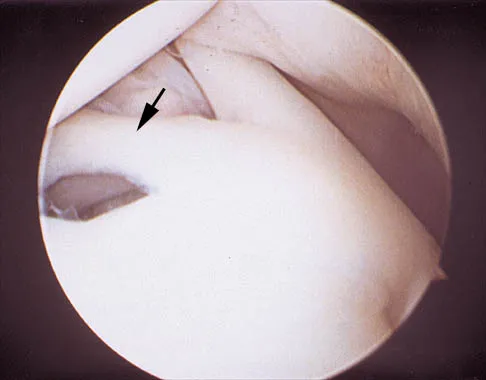

A 24-year-old athlete has a painful right shoulder. Figure 30 shows an intra-articular photograph that was obtained through a posterior portal during arthroscopy; the labrum is indicated by the arrow. Based on these findings, management should consist of

Explanation

The photograph shows a normal variant that is a sublabral hole beneath the anterosuperior labrum. In some instances, the labrum will become confluent with the middle glenohumeral ligament as a stout band. Because this variant is not abnormal, no treatment is necessary. Securing this portion of the labrum to the capsule may tighten the middle glenohumeral ligament complex and restrict external rotation of the arm. Andrews JR, Guerra JJ, Fox GM: Normal and pathologic arthroscopic anatomy of the shoulder, in Andrews JR, Timmerman LA (eds): Diagnostic and Operative Arthroscopy, ed 1. Philadelphia, PA, WB Saunders, 1997, pp 60-76.